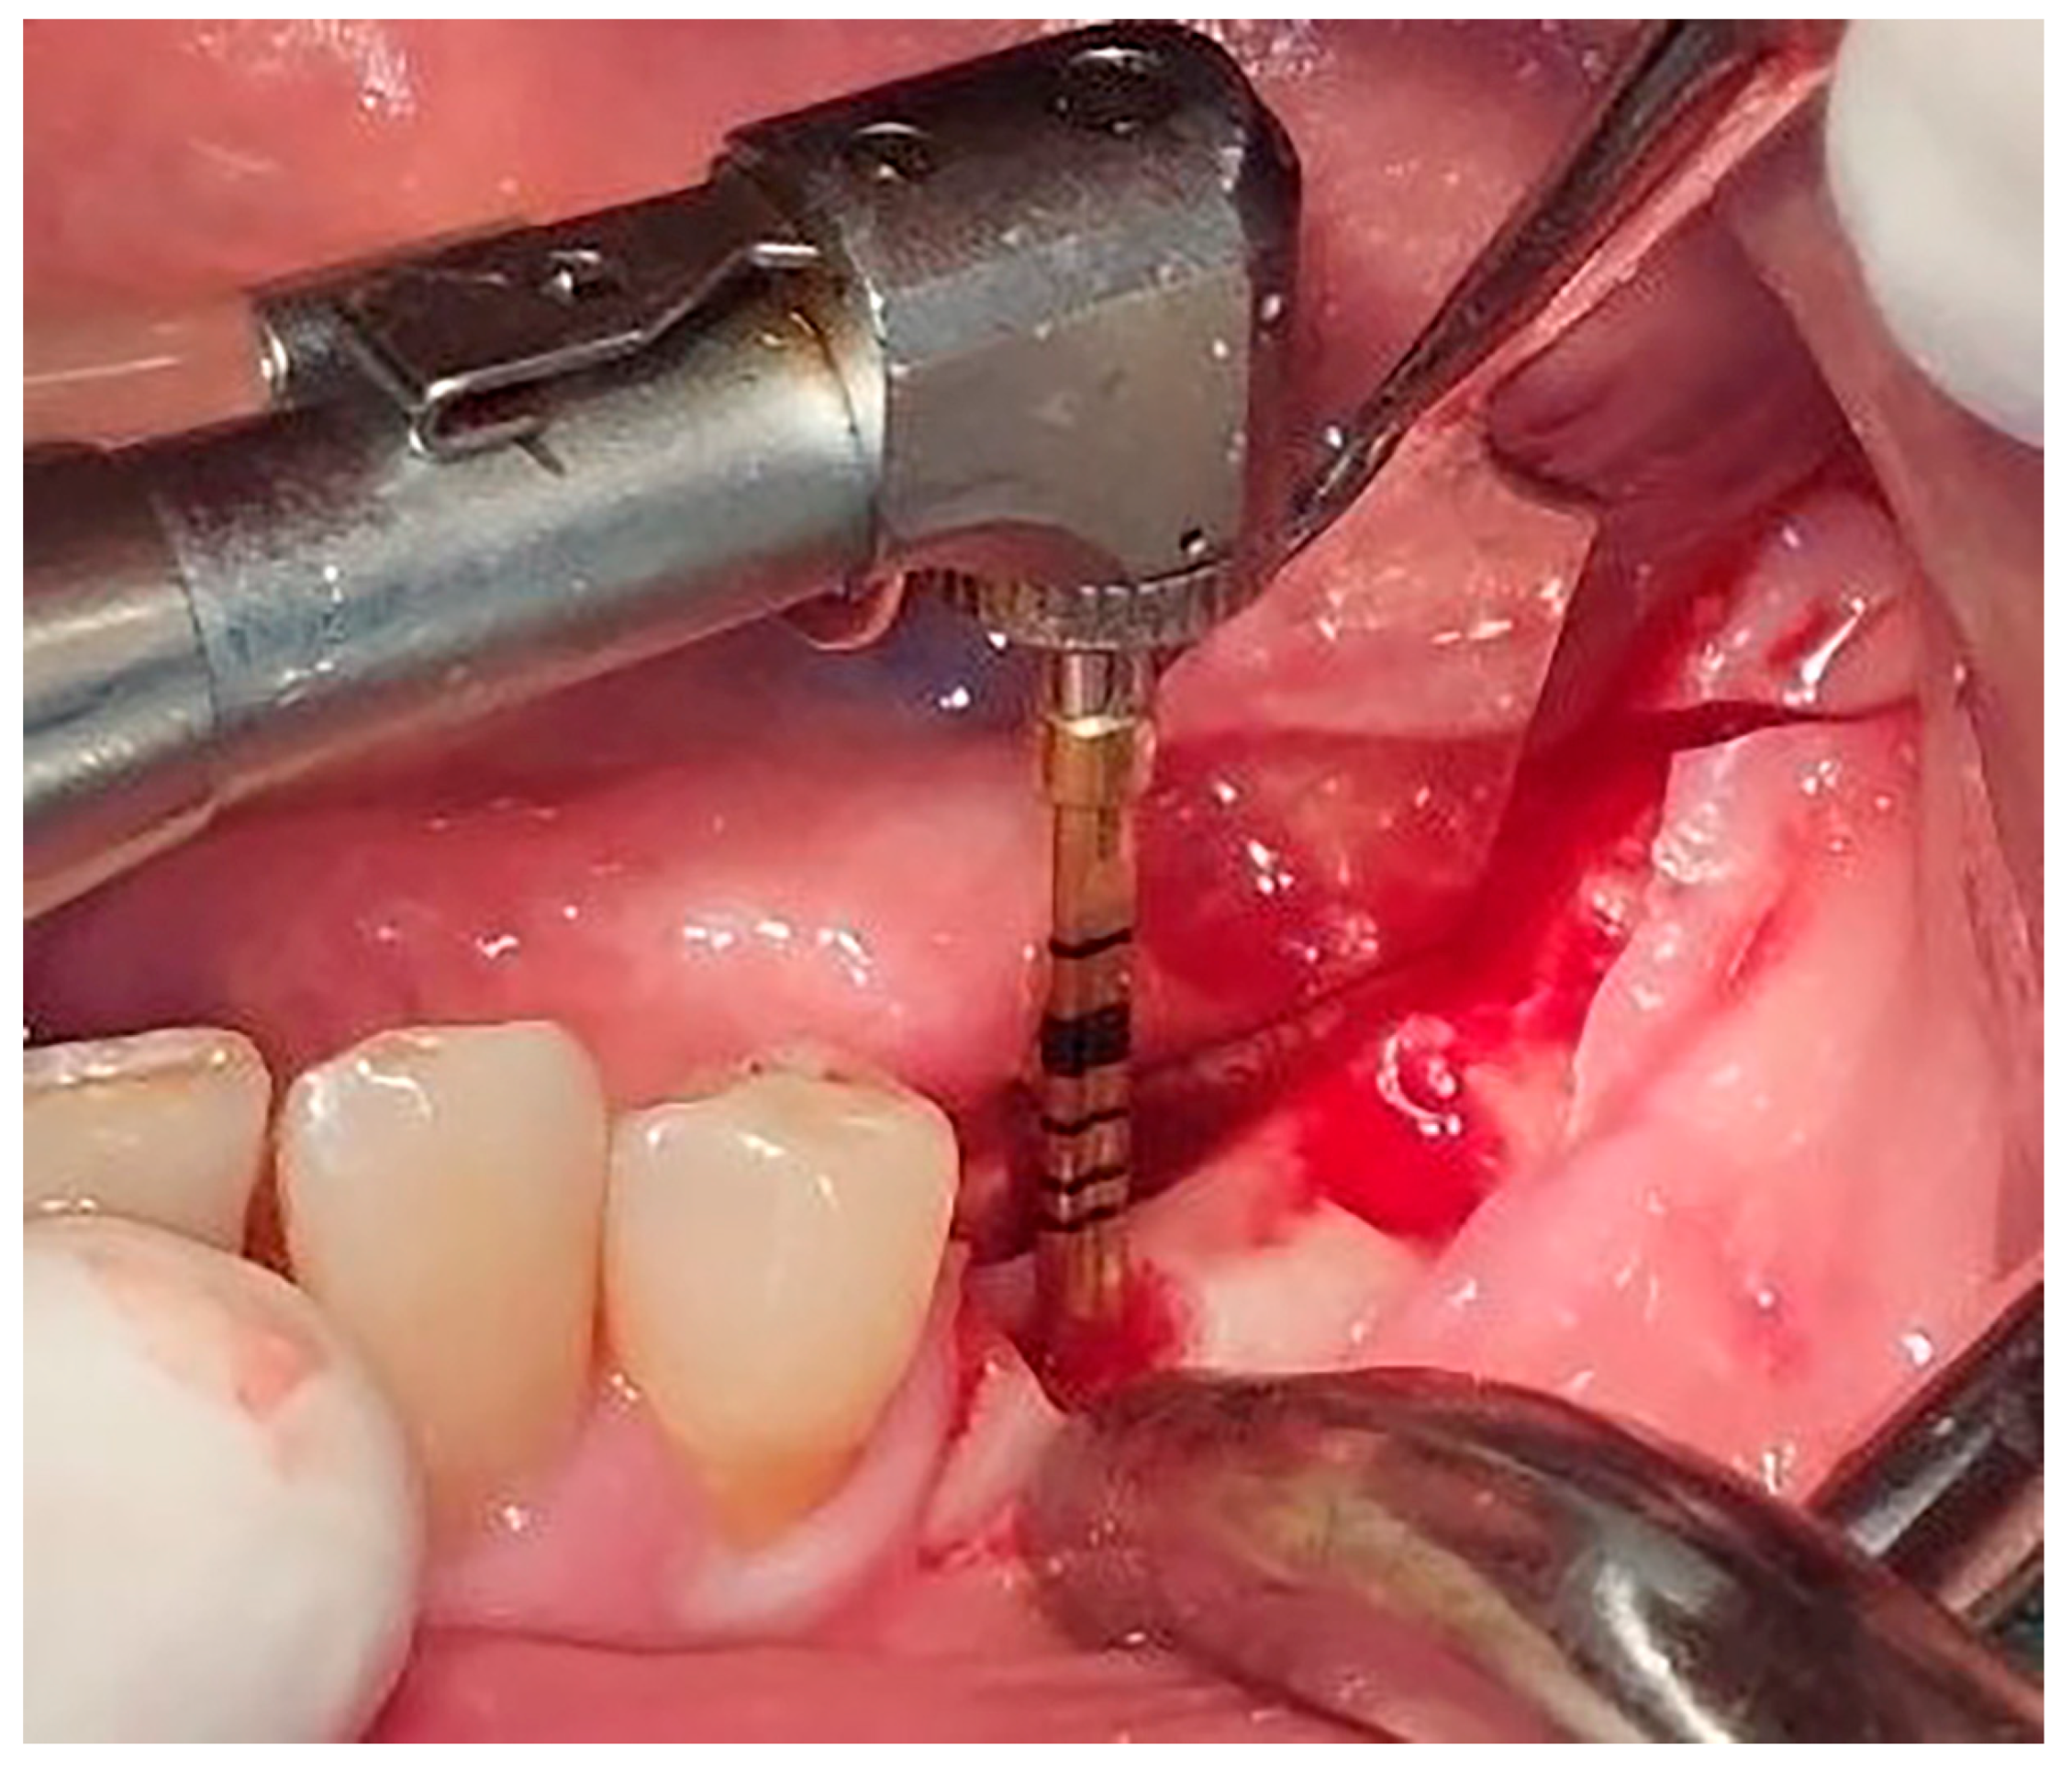

Local anesthesia using 4% articaine with adrenaline 1:100,000 (Septanest®, Septodont, Saint-Maur-des-Fossés, France) was administered. After the midcrestal longitudinal incision, a full thickness mucoperiosteal flap without a vertical releasing incision was elevated and the top of the alveolar ridge was flattened to the width of 4 mm (Figure 3). Preparation of the implant bed was performed with only one twist drill from the set (Esset kit®, Osstem, Seoul, Republic of Korea) which corresponded to the implant length (Figure 4). Following the preparation of the implant bed with the twist drill, a midcrestal longitudinal osteotomy was performed with a special saw with the speed of 1200 rpm (Figure 5). A specially designed set of expanders (Esset kit®, Osstem, Seoul, Republic of Korea) was used gradually in order to separate the buccal plate from the lingual cortical plate, according to their elasticity (Figure 6A–C).

Figure 4. Preparation of the implant bed.